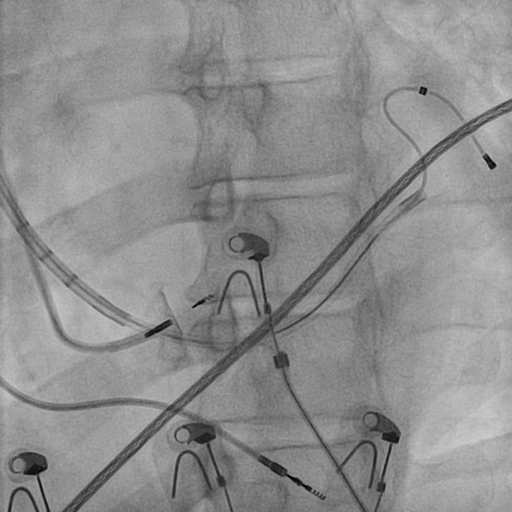

CS venogram

venogram_lao_rao.jpg

CS lead through subselective catheter

lead_subselective.jpg

Left bundle lead in place

LB_lead.jpg

Final position

final_position.jpg